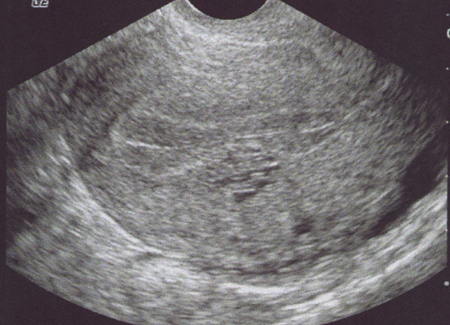

Fistule artério-veineuse au sein de l’endomètre après curetage (Cliché : Dr. C. TALMANT)